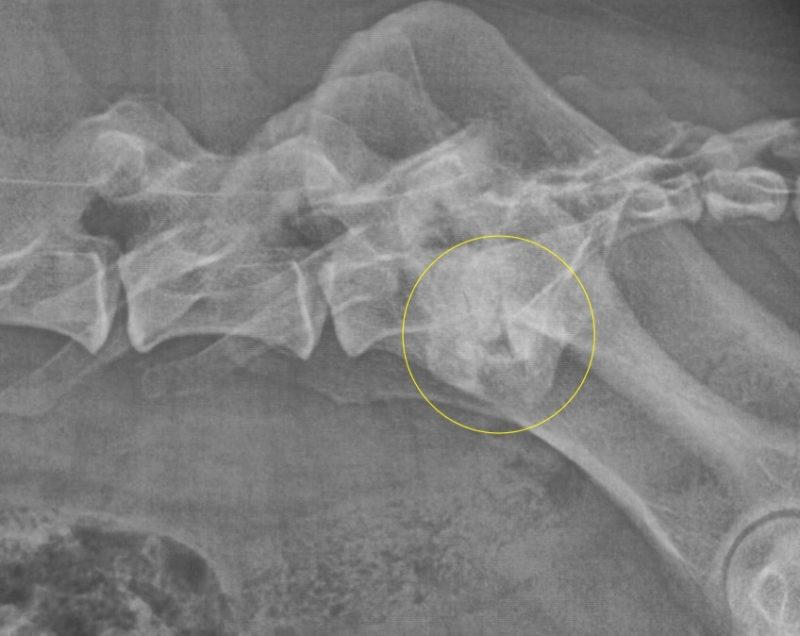

Nichts geht mehr? Urmels neue Menschen ergreifen den letzten Strohhalm. Ende April 2017 wird Urmel von ihrer Pflegerin Fatma nach Schweinfurt gefahren, um sie hier im Tiergesundheitszentrum näher zu untersuchen. Nach einer Gangbildanalyse (die bei einem so schwerfällig und nur mit Unterstützung einer Tragehilfe laufenden Hund natürlich nur eingeschränkt möglich ist) werden nach der anschließenden etwa zweistündigen orthopädischen Untersuchung aller Gelenke noch weitere Röntgenbilder von den Gelenken angefertigt, die in der Türkei nicht untersucht worden sind. Es zeigt sich, dass der Zustand noch schlechter ist als eh schon befürchtet: Urmel hat auch Arthrosen an der Wirbelsäule und weiteren Gelenken. Schließlich werden Urmel insgesamt 62 Berlock-Goldimplantate (das sind kleine spulenförmige Goldimplantate aus Dänemark) implantiert.

Infolge einer Gewichtsverlagerung bei solchen an einem Gelenk schwer gehandicapten Hunden kommt es über die Monate zu Folgeschäden an anderen Gelenken. Diese Schäden können sich bis zu den Zehengelenken ausdehnen. Häufig sehen wir dabei Arthrosen an den Zehengrundgelenken. Nicht selten sind die Sesambeine dieser Zehen frakturiert, durch Überlastung richtiggehend zerbröselt. Gerade solche Schäden aber werden leider zu oft übersehen. Wird eine solche Sesambeinfraktur übersehen, lahmt der Patient trotz aller weiteren Maßnahmen meist weiter. Da nutzt auch die beste Rekonstruktion der Patella am Knie nichts.